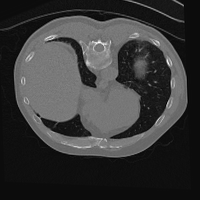

Exp. 3: Adult thorax data: To show the versatility of our approach we also apply it to adult thorax scans. For this experiment no organ specific training is performed but the whole volume is used. We evaluate reconstruction performance similar to Exp. 1 and prediction performance when is projected on an external plane, comparable to X-Ray examination using C-Arms. The latter provides insights about our method’s performance when applied to interventional settings in contrast to motion compensation problems. 60 healthy adult thorax scans were randomly selected, 51 scans used for and nine scans used for . Each scan is intensity normalised and resampled in a volume of with spacing . Using the Fibonacci sampling method, 25 sampling plane of size , evenly spaced between -50 and +50, were rotated over 500 normals. Training took approximately 20 hours for 60 epochs. Fig. 4c shows an example reconstruction result gaining 28dB PSNR with additional SVR. prediction takes approx. 20 ms/slice for this data.

0..5.3 Exp. 3:

We replicated the experiment on adult thorax data without specifically segmented organs. This approach was applied to CT acquisition, shown in Fig 13 and 14, as well as Digitally Reconstructed Radiographs generated using Siddon-Jacobs Ray Tracing shown in Fig. 16.